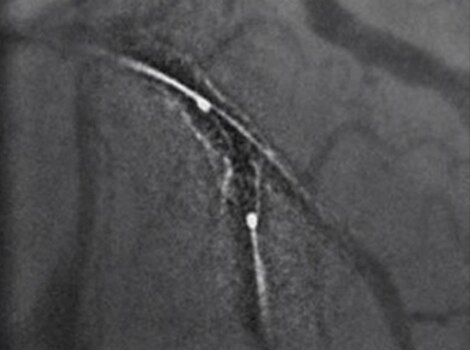

Intervention

Successful PCI of the stenotic lesions involves planning, guidance, and assessment of the culprit lesion and assessment of the remainder of the coronary tree.

Innova IGS 55

Helps reduce use of contrast and dose with one of the industry’s highest ratings for Detective Quantum Efficiency (DQE).

PCI ASSIST6

Help plan, assess and guide interventional procedures with improved visibility up to 85 percent in moving anatomy.